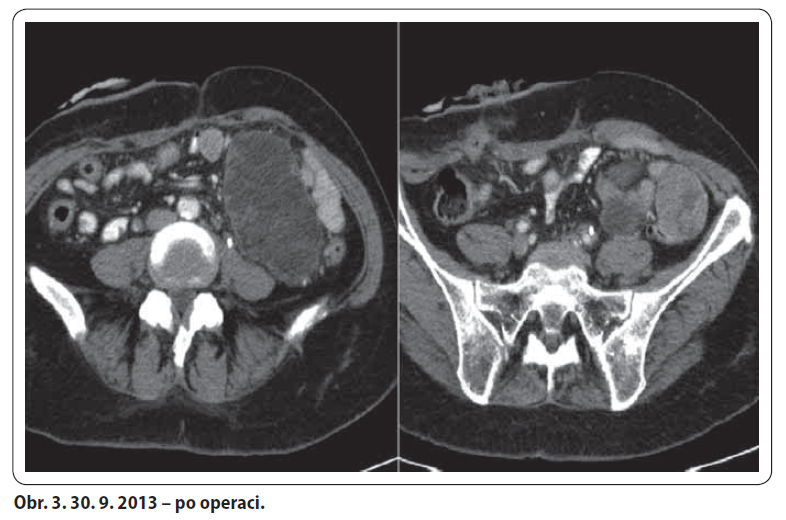

57letá žena, bez komorbidit a chronické medikace, došetřována od ledna 2012 pro chřipkové příznaky a váhový úbytek 10 kg. Proveden UZ břicha a gynekologické vyšetření s nálezem hypoechogenního útvaru v malé pánvi. Následně laparotomie s ovarektomií, kde v oblasti levé ovariální fosy tumor retroperitonea fi xující levý vaječník a vejcovod, potvrzeno i na CT. Histologicky dobře diferencovaný smíšený mezenchymální maligní tumor. 19. 7. 2012 v MOÚ Brno exstirpace nejasně ohraničeného tumoru (130 × 100 × 80 mm) spolu s hysterektomií. Histologicky high-grade polymorfocelulární sarkom bez bližší orgánové specifikace. Následně adjuvantní RT v KOC Zlín v dávce 46,8 Gy/ 26 fr. na malou pánev a 59,4 Gy/ 33 fr. na lůžko tumoru. Po ukončení RT pro bolesti zad provedeno CT. Na něm nově objemné expanzivní útvary mezi střevními kličkami a v levém mezogastriu – suspektní metastázy. V 1/ 2013 revize dutiny břišní v MOÚ Brno – nález inoperabilní, provedena paliativní spojková operace a vyvedena ileostomie. U pacientky s dobrým PS tedy indikována první linie paliativní CHT Adriamycin 3W. Od 2/ 2013 do 6/ 2013 bylo podáno celkem šest sérií se zajištěním filgrastimem pro neutropenie grade III. Dle CT přešetření bylo dosaženo parciální odpovědi. Z onkochirurgické komise KNTB pacientka indikována k operačnímu výkonu. 20. 8. 2013 byla provedena maximální debulking operace. Pooperačně CT i PET/ CT negativní. Poté podány tři série zajišťovací chemoterapie Adriamycin 3W s profylaktickým podáním filgrastimu. Kontrolní CT bez známek recidivy tumoru. V 3/ 2014 zanoření ileostomie. Dle CT restagingu z 5/ 2014 a 11/ 2014 trvá kompletní odpověď.